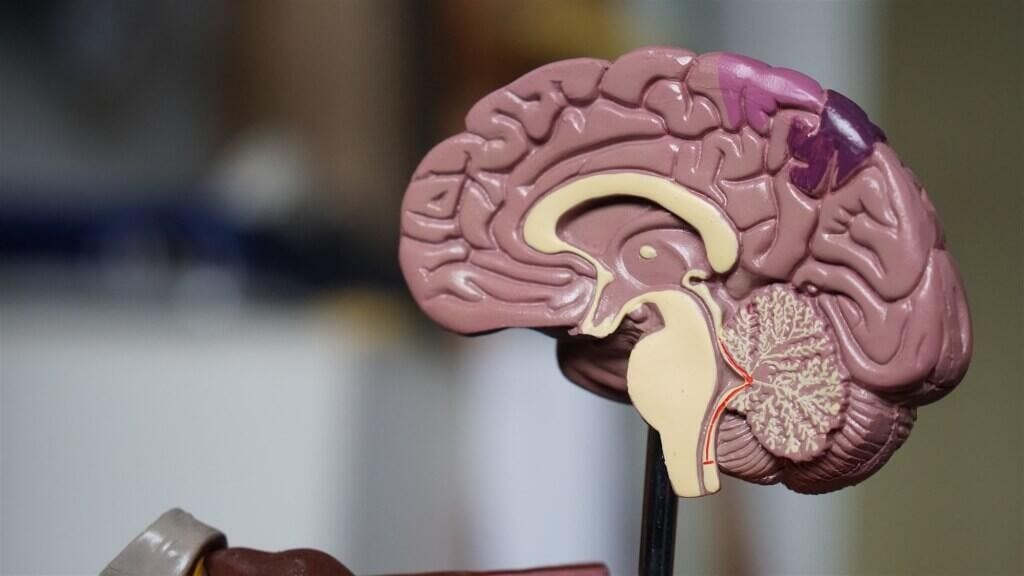

由於噪音不僅對人產生不舒適,也會造成聽力受損,現在許多藍牙無線耳機都會搭載主動降噪技術,用戶也經常在通勤、辦公室、公眾場合等環境啟用主動降噪減少不舒適感;但根據英國BBC報導指稱,英國聽力學學家推測時間暴露在主動降噪卻可能帶來稱為APD的聽覺處理障礙問題,具體來說就是影響大腦處理口述語言的神經系統疾病。 BBC引述一位名為蘇菲的25歲行政助理的故事,她經常被罵不專心聽話、心不在焉,她指稱儘管她聽得到口述聲音的形體,卻無法清楚且快速判斷對方口述的內容;經過聽力學家診斷後,蘇菲即是具有APD問題的患者;根據蘇菲的說法,她是在大學期間才留意到自己聽力發生問題,具體來說是無法判斷聲音的方向。 蘇菲的說